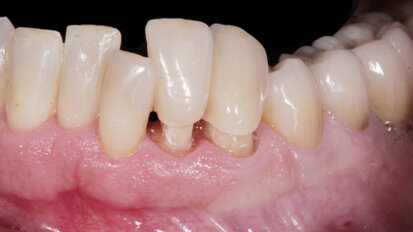

Rehabilitace Straumann